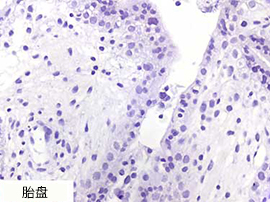

使用 Enzo's AMPIVIEW™ RNA 探针时,SARS-CoV-2 阴性组织无背景染色

|

AMPIVIEW™ SARS-CoV-2 RNA探针 |

AMPIVIEW™ SARS-CoV-2 RNA探针 |

竞品的SARS-CoV-2 RNA探针 |

|

|

|

|

|

"使用其他品牌探针和Enzo AMPIVIEW™ 探针通过ISH检测了一些正常的大脑和胎盘作为SARS-CoV-2 RNA的阴性对照。对比竞品探针的背景(红细胞),使用Enzo探针的背景低。" ——Dr. Nuovo, 俄亥俄州立大学 |